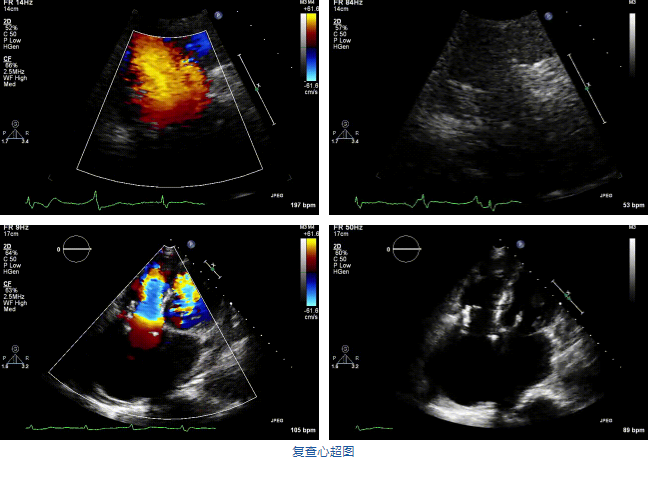

結合術前CT評估結果,葛均波院士團隊最終決定選用LuX-Valve Plus 50mm和55mm兩種型號的瓣膜,并于2021年11月30日順利完成LuX-Valve Plus經血管三尖瓣置換術,手術室即刻拔除氣管插管,術后第二天轉出心內科監護室,下床活動。術后患者三尖瓣反流癥狀得到顯著改善,復查心超結果顯示人工三尖瓣瓣膜支架固定穩定,瓣葉關閉形態未見異常,未見明顯反流。